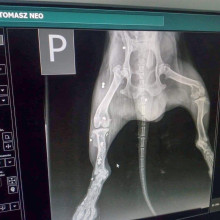

Zabrali więc Neo do weterynarza. Jak się okazało, pies został nafaszerowany śrutem przez jakiegoś zwyrodnialca. W ciele zwierzęcia tkwi co najmniej 20 kul, w tym jedna w… kręgosłupie.

Lekarz weterynarii – ze względu na wiek czworonoga – nie chce wyciągać kul, bojąc się o życie pacjenta. (Piesek mógłby po prostu nie przeżyć takiej operacji).